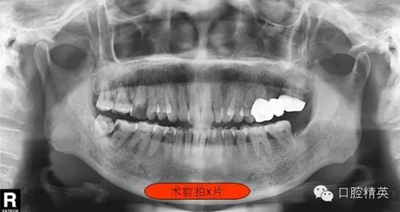

右下7根管治療(C型) 科貿嘉友收錄

這位患者女性,年齡60歲。遠中鄰面深齲,探診疼痛不適。主訴有夜間疼痛加重,叩診(+),一度松動,遠中根部牙槽骨吸收,診斷牙髓炎。后來右下8拔除。